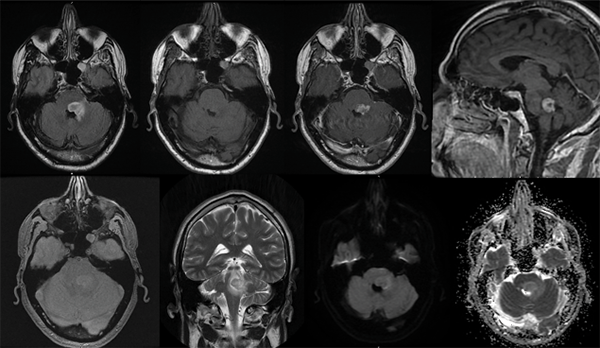

La tomografía computada (TC) de encéfalo reveló una imagen hipodensa a nivel protuberancial (Fig. 1) caracterizada mejor en resonancia magnética (RM) donde se observó en topografía tronco encefálica a nivel protuberancial medial y paramedial izquierda la presencia de una lesión expansiva que deforma el contorno anterior del cuarto ventrículo y se proyecta sobre el pedúnculo cerebeloso medio (Fig. 2). La lesión genera efecto de masa del sector, presenta naturaleza sólida, señal de resonancia heterogénea en su interior, contornos parcialmente definidos con un diámetro longitudinal de 14 mm, diámetro transversal de 17 mm y diámetro anteroposterior de 16 mm. La lesión es hiperintensa y heterogénea en secuencia T2 y FLAIR e hipointensa en T1, con edema perilesional tal cual son puestos de manifiesto en la imagen T2 coronal, que involucran la protuberancia y el mesencéfalo izquierdo. La lesión ocupante de espacio no mostró netarestricción en las secuencias moleculares de Difusión y ADC. No mostró cambios en la señal en la secuencia T2-GRE (Fig. 2).

Fig. 2. A: Axial-FLAIR. B: Axial-T1 sin gadolinio. C: Axial-T1 con gadolinio. D: Sagital-T1 con gadolinio. E: T2*- GRE F: Coronal-T2 G: Difusión. H: ADC